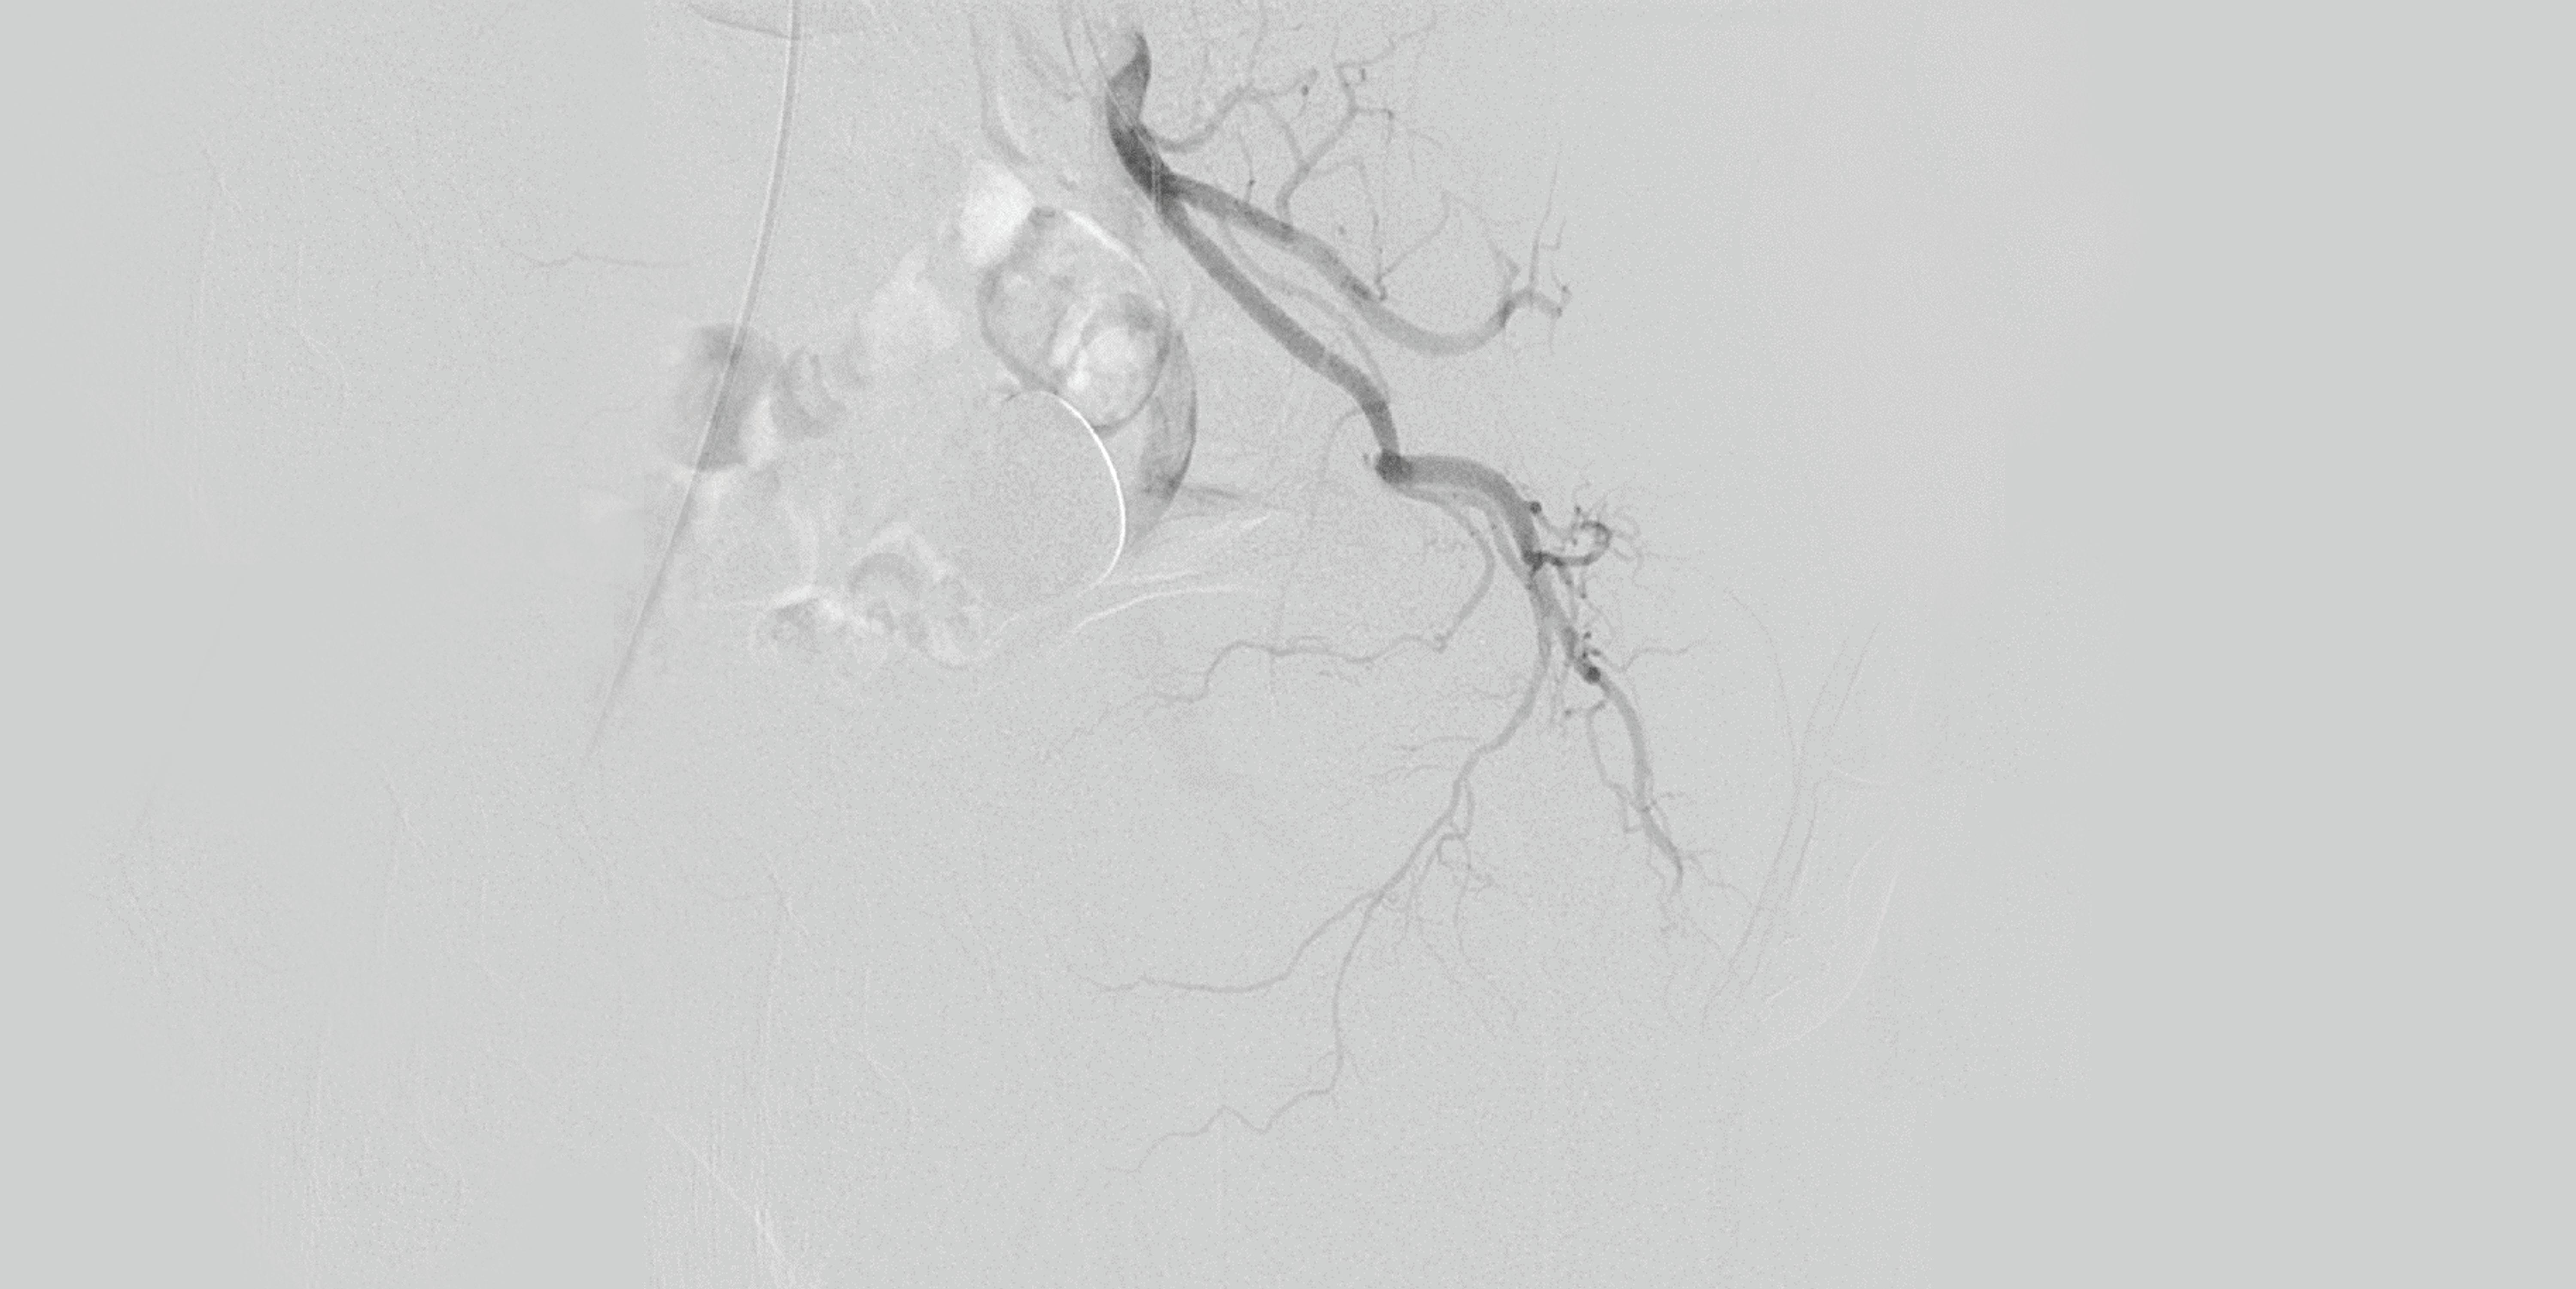

In their analysis, Powell and colleagues analysed the causes for ETF in both cohorts, the impact on major adverse limb events (MALE), above ankle amputation, death and major adverse cardiovascular events (MACE: defined as myocardial infarction, stroke and serious cardiovascular adverse events). ETF was defined as the inability to successfully complete the initial endovascular procedure.

“We approached this with an open mind,” details co-investigator John Kaufman (Oregon Health and Science University [OHSU] in Portland, USA). “We were interested that proximal SFA [superficial femoral artery]

occlusion, which was such an influential determinant, and that failure to cross the lesion was far more common than dissection, residual stenosis, or distal embolization as a failure mode.”

The investigators also analysed lesion location, which Powell highlights as a strength of their trial. In determining this, he hopes that granular predictions can be developed for patients that are less likely to achieve technical success, to map potential failure modes for each specific case.

SIR 2024 in Salt Lake City, USA, due to the significant influence ETF had on outcomes in the BEST-CLI dataset, and on real-world endovascular practice. He adds that their results will likely stimulate even more questions in an attempt to elucidate the reasons for ETF even further. “We anticipate some difficult and maybe even some sceptical audience questions at the SIR annual meeting” he speculates.

Taking this in stride, Kaufman views that this is all an essential part of science and important research, but there are questions that they will not be able to answer yet, such as the morphology of uncrossable occlusions that cause ETF. “We don’t yet know whether these are flush or heavily calcified, nor the specifics of the techniques used to attempt to cross the lesions. I think we all approach occlusions with a measure of respect, and these results support that.”